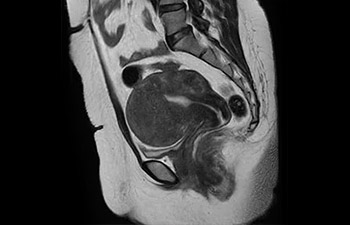

En una sociedad en la que los reembolsos son cada vez menos cuantiosos y las enfermedades crónicas se traducen en un aumento de los procedimientos de RM y en tiempos de espera más largos, los servicios de radiología se ven sometidos a una presión cada vez mayor. La aceleración pone en riesgo la calidad de la imagen o bien se puede aplicar a todo el espectro de las exploraciones rutinarias. Por lo tanto, para satisfacer la creciente demanda de productividad, todavía es necesario dar un paso adelante más en cuanto a la aceleración. Aprovechando nuestra dilatada posición de liderazgo en el ámbito de la velocidad (de la mano de SENSE), Philips presenta Compressed SENSE, un avance en términos de productividad.

• Es una innovadora técnica de aceleración que no solo permite agilizar las secuencias, sino todo el estudio. • Implementación especial con la que las exploraciones en 2D y 3D pueden llegar a ser hasta un 50% más rápidas con una calidad de imagen prácticamente equivalente.1

• Se puede usar con todos los contrastes y con todas las regiones anatomías.